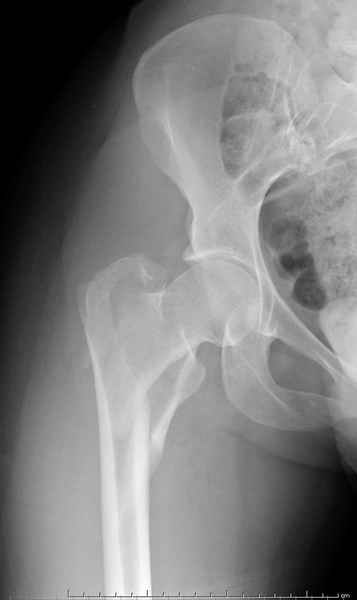

Для молодых больных выбрал бы тактику fixed angled device 95 degree Blade Plate, техника непрямого метода репозиции, который описал в своей книге Jeff Mast, Planning and Reduction Technique in Fracture Surgery ( method of Inderect Reduction), репозиция и фиксация происходит за счет фиксации головки бедра к femoral shaft с помощью пластины, а что в середине должны репонироваться без больших усилии и без разрушения мягкотканого соединения c медиальной стороны.

Ap pelvis Rt sub-intra trochanteric Fracture, AP Rt hip, Postop Blade Fixation